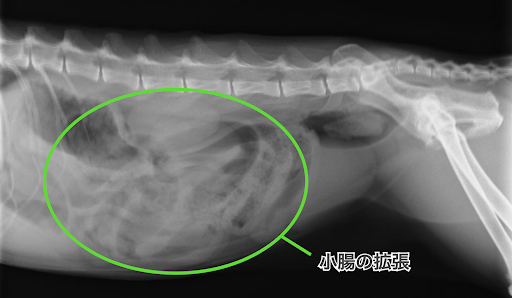

レントゲン検査では小腸の拡張とガスによる膨満が確認されました。

こちらがレントゲン画像です。